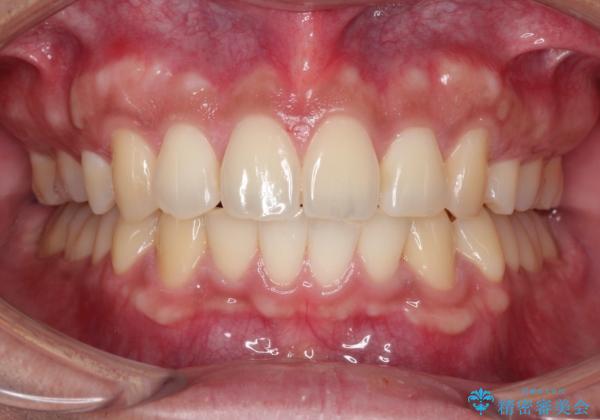

【審美ワイヤー】奥歯のガタガタを治したい

- 歯並びの凸凹を主訴に来院されました。

スペースが必要なため、抜歯を行なって治療を行いました。

奥歯の捻れが強く治療期間がかかりましたが、綺麗な仕上がりに満足していただきました。